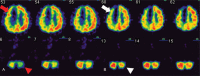

Rationale: Crossed cerebellar diaschisis (CCD) is a poor prognostic factor after stroke because without immediate cerebral reperfusion no further improvements in the patient's condition can be achieved. We investigated the clinical effects of intravascular laser irradiation therapy (ILIB) on CCD and evaluated the therapeutic effect in the sub-acute post-stroke stage.

Outcomes: We used single-photon emission computed tomography (SPECT) before and after intravascular laser irradiation to detect changes in cerebral and cerebellar perfusion. Then, we compared the two images. CCD was detected using the first SPECT. After intervention by ILIB, the second SPECT showed greater perfusion in the affected cerebellar hemisphere.

Lessons: We found that ILIB helped eliminate CCD, which was previously shown to be an untreatable condition using any intervention during the sub-acute post-stroke stage. Stroke patients could therefore greatly benefit from ILIB.